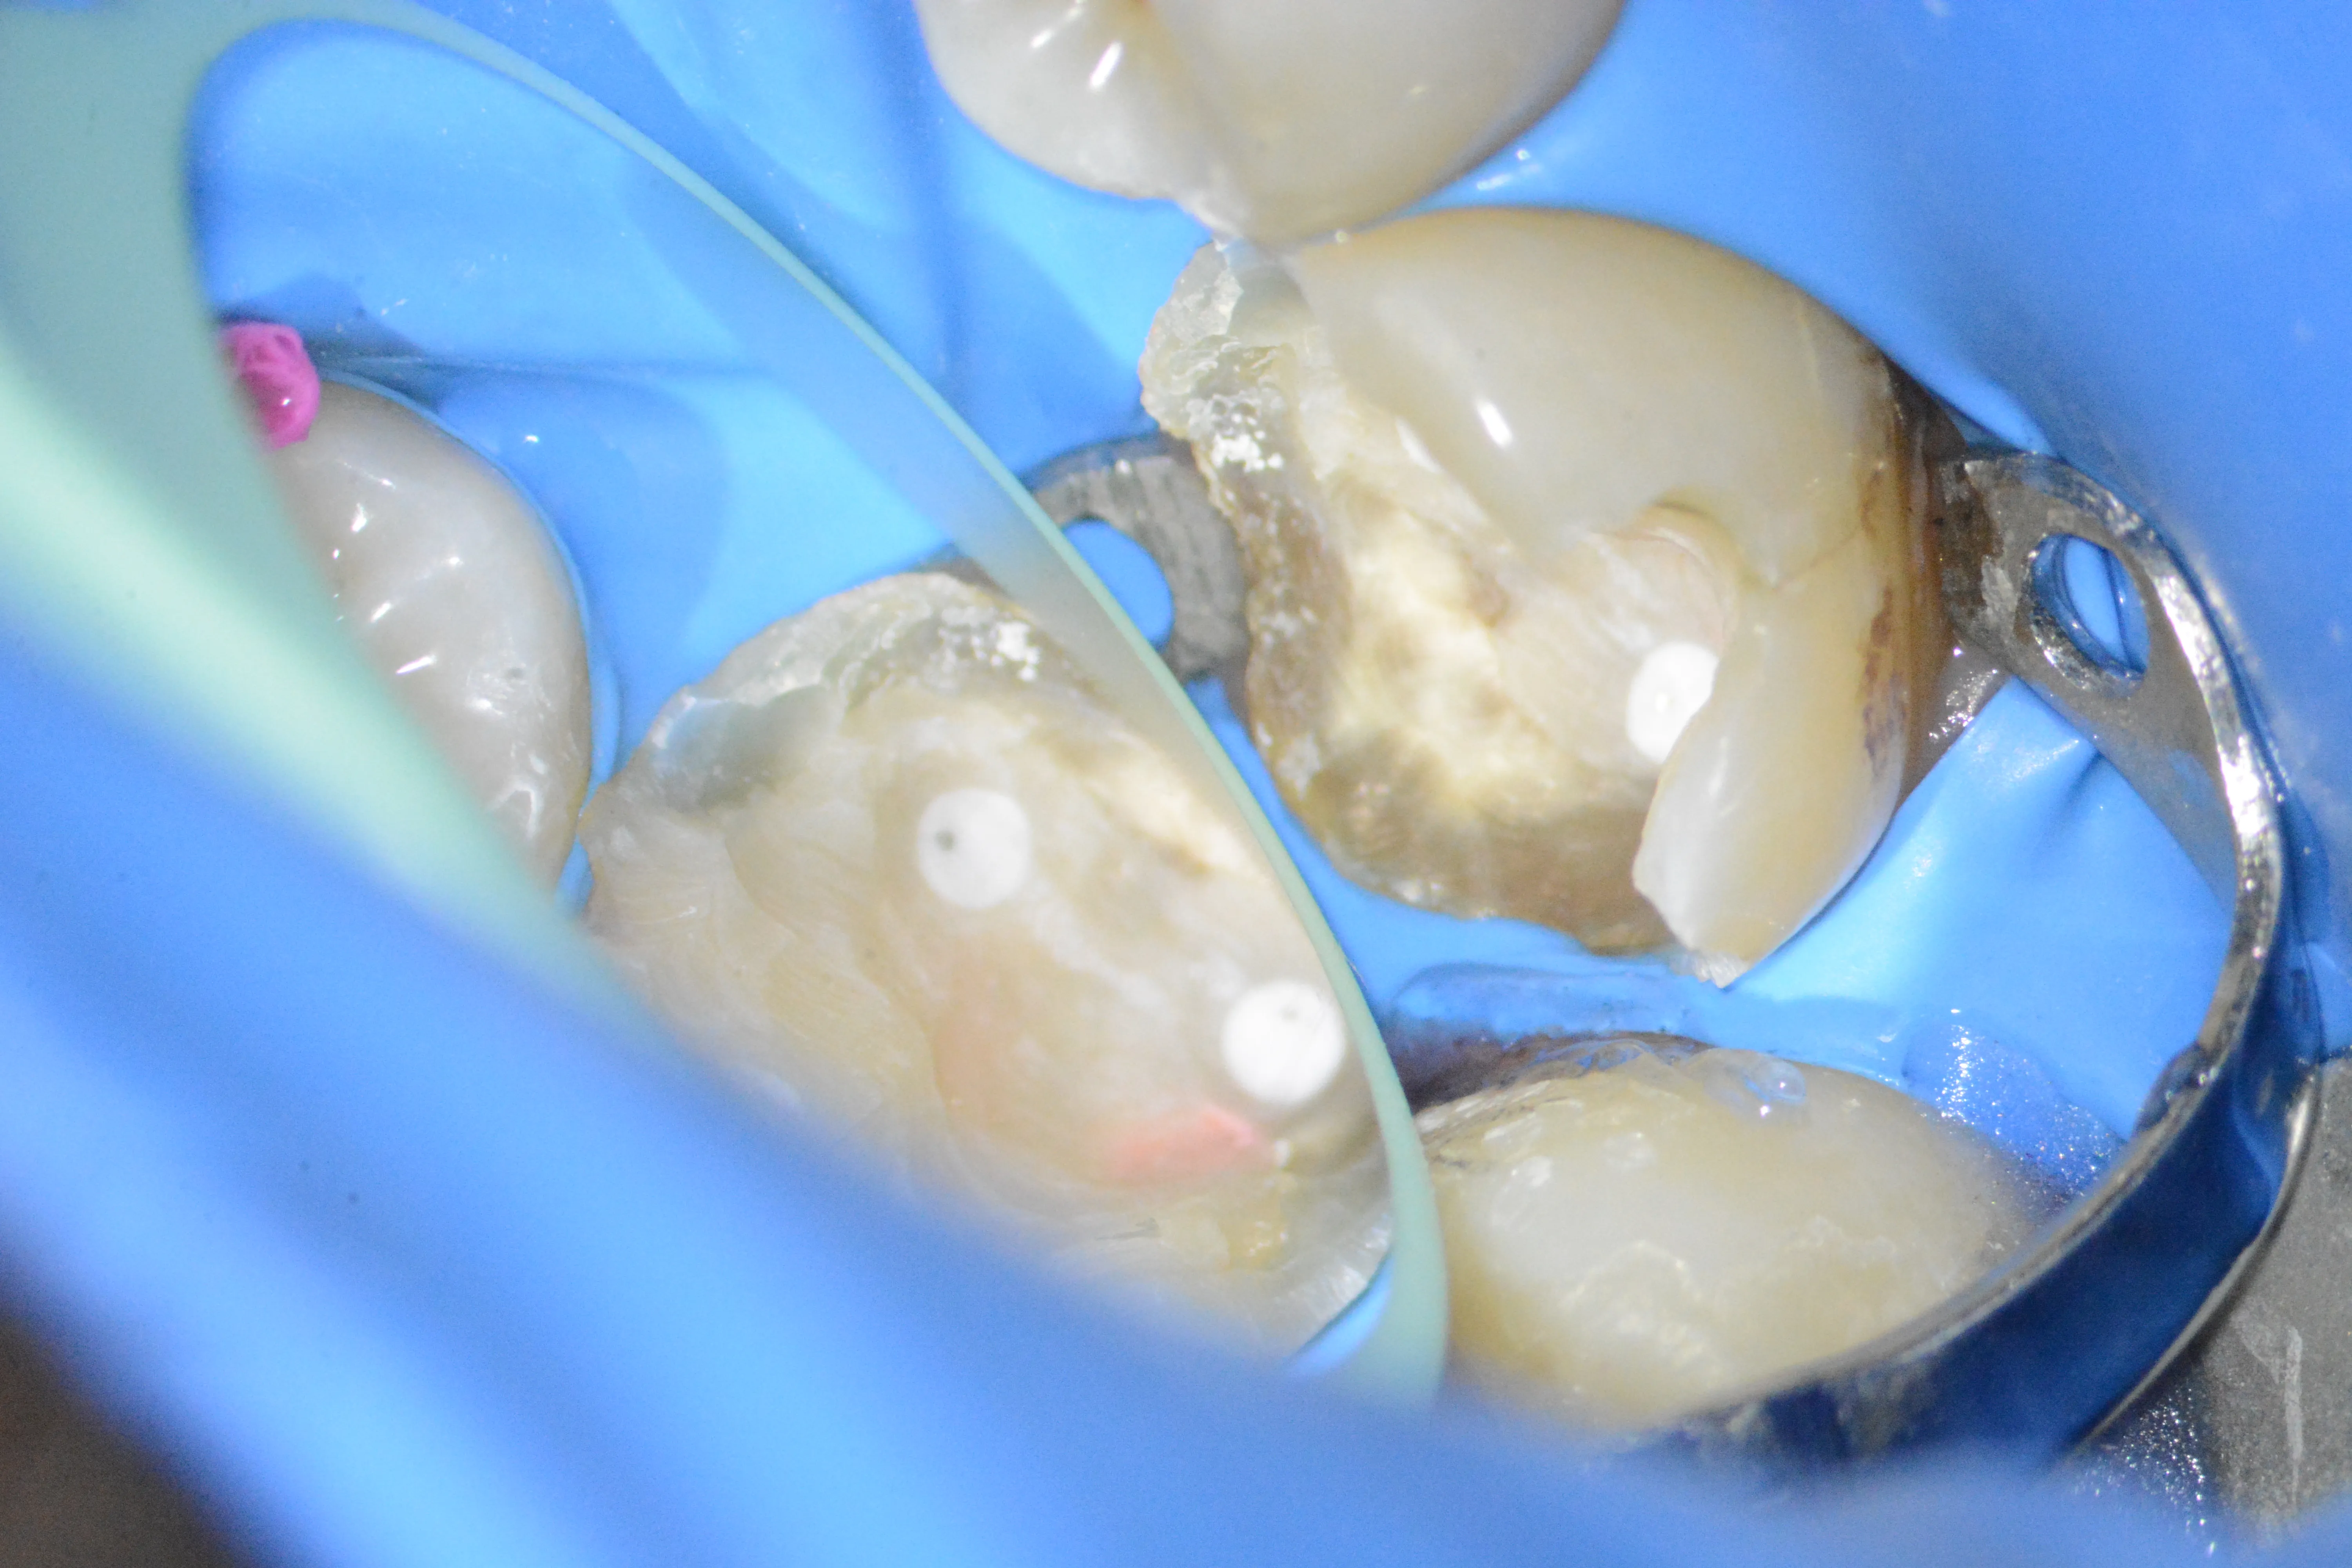

3 – Izolare deficitară

4 – Aplicare clemă de digă accesorie